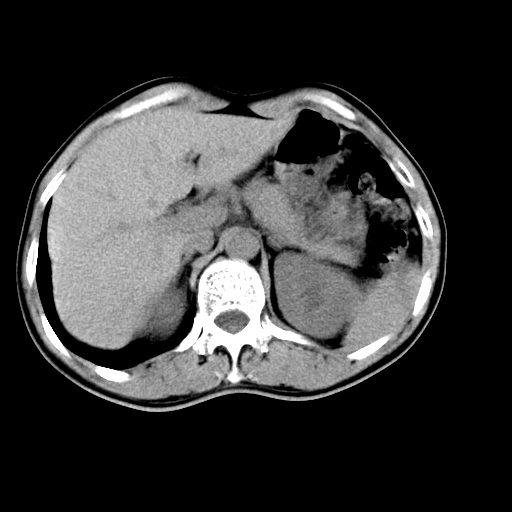

男,47岁,左输尿管结石碎石治疗后10余日。彩超示:左输尿管下段狭窄、输尿管积水。请各位讨论一下左输尿管下段结石还是静脉石?

象是第二狭窄处结石伴以上输尿管、肾盂轻度积水。

输尿管结石伴以上输尿管、肾盂轻度积水。

两侧髂总动脉壁斑状及点状钙化.左侧输尿管行经与左髂总动脉相交后见高密度影,且下段输尿管管腔未见扩张,应该要考虑结石伴以上输尿管及肾盂积水.但右侧结节状高密度影,也应该是结石吧!那以上输尿管未见扩张呢!因此静脉结石可能性也较大.请问楼主碎石前左侧输尿管结石位置.

虽左侧有轻度肾盂积水但不支持结石。1结石边周应该有软组织包绕呈晕征。2钙化点前面见输尿管影也不支持是结石。3彩超没提结石。建议超生复查。

输尿管先位于腹部,后进入盆腔,最后斜穿膀胱壁开口于膀胱,因此,临床上常将输尿管分为腹段、盆段和壁内段。第1个狭窄:在肾盂与输尿管移行处。第2个狭窄:在跨过髂血管处。第3个狭窄:在穿过膀胱壁处。这些狭窄是结石容易滞留的部位。